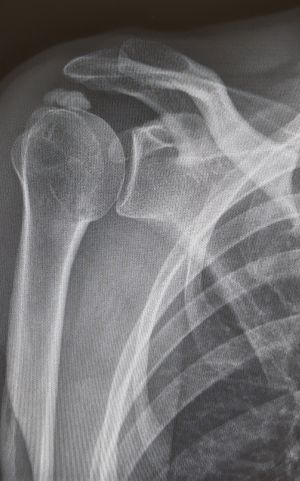

Durch Sturz auf die Schulter kann es zur Sprengung des Acromioclaviculargelenkes (AC-Gelenkes, Schultereckgelenkes) kommen. Hierbei entsteht durch Bänderrisse ein Höhertreten des Schlüsselbeins.

Durch die Sprengung des Gelenkes kommt es zu einem schmerzhaften Höhertreten des Schlüsselbeines. Neben dem klinischen Befund ist ein konventionelles Röntgen ausreichend.